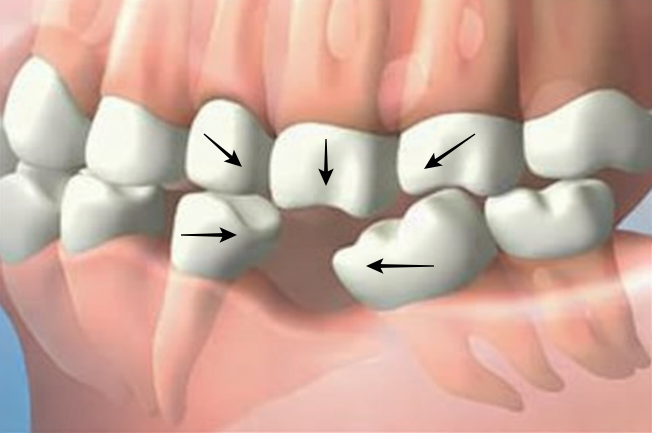

도미노처럼 쓰러지는 치열

빈 공간으로 양옆의 치아들이 기울어지기 시작합니다. 치아 사이 틈이 벌어지면서 음식물이 쉽게 끼고, 이는 멀쩡했던 인접 치아의 충치와 풍치를 유발하는 연쇄 작용을 일으킵니다.

맞물리는 치아의 이탈(정출)

상실된 치아와 맞닿던 반대편 치아가 공중으로 솟거나 내려오는 현상이 발생합니다. 나중에 임플란트를 하려 해도 이 정출된 치아 때문에 공간이 없어 멀쩡한 치아를 깎아야 하는 상황에 직면합니다.